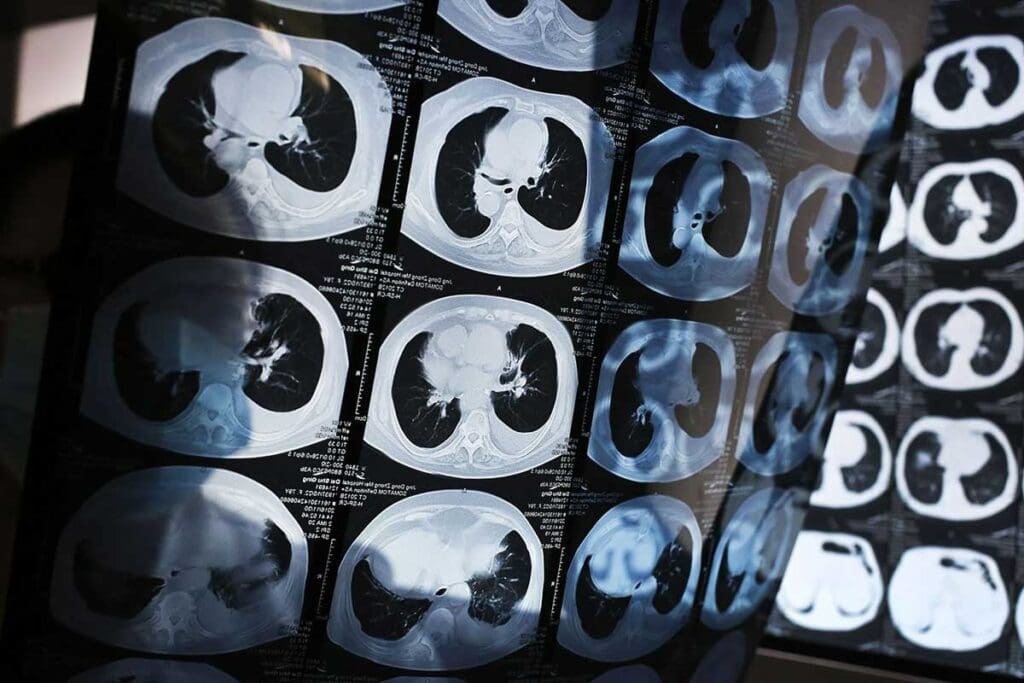

Lung Cancer: The Most Deadly Worldwide

Lung cancer is the top cause of cancer deaths worldwide. It leads to more deaths than any other cancer type.

Why Lung Cancer Remains the Top Killer

Lung cancer is the biggest killer of cancer worldwide. It’s because it’s often caught late and is very aggressive. We must push for more smoking cessation programs and early tests to fight it.